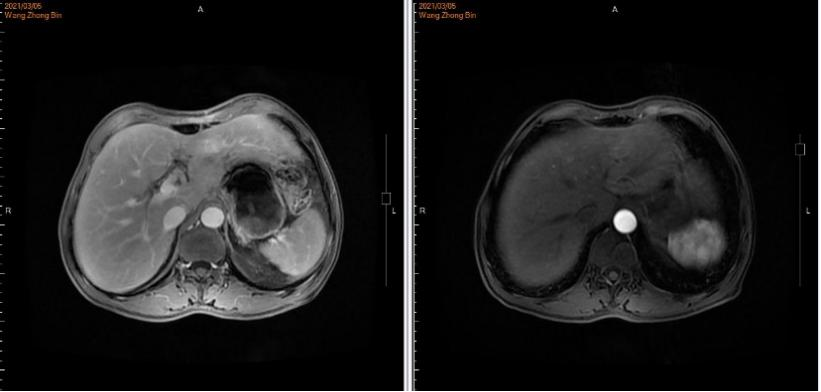

▌病例作者:大连医科大学附属第一医院 李颖 教授 ▌点评专家:大连医科大学附属第一医院 张洁 教授 编者按 ●我国是胃癌大国,根据世界卫生组织国际癌症研究机构(IARC)发布的2020年中国最新癌症负担数据:2020年中国癌症新发病例457万例,其中胃癌48万例位居第三;2020年中国癌症死亡人数300万,其中胃癌37万,位居第三[1]。70%的胃癌患者确诊时为局部进展期或进展期胃癌。其中HER2阳性胃癌是一类高度异质性肿瘤,侵袭性强、复发率高、预后不良。国内胃癌HER2阳性率的多中心研究结果显示,中国人群胃癌HER2阳性率为12~13%。ToGA[2]研究证实,曲妥珠单抗联合化疗能显著提高HER2过表达晚期胃癌患者治疗反应率,改善患者生存状况,因此曲妥珠单抗被推荐用于HER2过表达晚期胃癌的一线治疗。肝脏是胃癌血行转移最常见的靶器官,胃癌肝转移的总体发生率约9.9%~18.7%。本文通过一例赫赛汀®转换为汉曲优®治疗HER2阳性晚期胃癌伴肝转移的病例,向大家介绍汉曲优®(曲妥珠单抗)在治疗HER2阳性晚期胃癌伴肝转移患者的临床获益情况。(注:本文中汉曲优®为复宏汉霖研发生产的曲妥珠单抗) 病史简介 患者:王某,64岁,男,身高180cm ,体重60kg ,BMI 18.52。 主诉:胃癌姑息术后1年余。 既往史:既往体健,否认吸烟史、饮酒史。 家族史:否认家族性遗传病、传染史。 查体:全身皮肤粘膜无黄染,全身浅表淋巴结不大,腹部可见手术瘢痕,质软,无压痛,肝脾肋下未及,未触及包块,移动性浊音阴性。 ▌影像学检查: 2021年1月21日腹部CT:胃窦癌征象,伴胃周、腹膜后增大淋巴结,请结合临床;肝右叶肝内胆管结石或钙化灶;左侧肾上腺强化不均。 图1.腹部CT 2021年1月22日胃镜示:胃窦环幽门见一溃疡型病变,致管腔狭窄,镜身无法通过。 图2. 胃镜 ▌肿瘤基本病理: 2021年1月25日:全麻下腹腔镜姑息性远端胃大部分切除D2廓清 B-Ⅱ+Braun消化道重建肝部分切除术。术中见:肝左外叶见1枚约1*0.5cm灰白结节,肿瘤位于胃下部,大小8*6cm,侵及胰腺被膜,NO.6组淋巴结肿大。 ▌胃术后病理: 胃溃疡型中低分化管状腺癌,大小4.7*3.7cm,侵及全层,脉管癌栓,神经侵犯;纤维脂肪组织内见淋巴结转移一枚,送检(6、7.8a、9组)淋巴结见转移癌(5/17),并见癌结节一枚。送检(1.3组、4sb组)淋巴结未见转移癌(0/6)。 ▌免疫组化: GST-π:(+),HER-2:(3+),Ki67:(+80%),MLH-1:(表达),MSH-2:(表达),MSH-6:(表达),PMS-2:(表达),P53/ target=_blank class=infotextkey>P53:(突变型)。 ▌肝术后病理: 肝内见中分化管状腺癌,大小为0.9*0.6*0.7cm,结合病史及免疫组化结果考虑为胃腺癌转移来源,累及肝被膜,未见明确脉管及神经侵犯。免疫组化:ARGINASE-1(-)、CDX-2(少许+),CK19(+)、CK20(-)、CK7(+)、GPC-3(部分+)、Hep-par(少许+)、Ki67:(+75%)、muc-5AC(+)、SATB2(-)、villin(+)。 ▌术后病理: 胃溃疡型中低分化管状腺癌淋巴结转移(图3左),肝内见中分化管状腺癌考虑为胃腺癌转移来源(图3右)。 图3 术后病理 诊断:胃癌姑息术后(pT3N2M1)PLVN+、Her-2过表达、pMMR型,同时性肝转移癌术后,肝转移癌(肝左叶单发)。 治疗经过 2021年1月25日:全麻下腹腔镜姑息性远端胃大部分切除 D2廓清 B-Ⅱ+Braun 消化道重建肝部分切除术。 2021年3月5日术后化疗时上腹部增强MRI发现疾病进展,出现新发肝转移癌。MRI示:胃体积减小,肝脏局部体积减小,肝左叶见一类圆形轻度环形强化影,平扫显示不清,最大径约16.6mm。诊断建议:肝、胃术后改变,肝左叶环形强化影,新发肝转移。(图4) 图4. 上腹部增强MRI 2021年3月3日起行一线曲妥珠单抗联合AS方案化疗: 具体:赫赛汀®:440mg 首周期剂量,360mg 后续周期剂量,7周期,因经济原因和患者体重下降原因调整为汉曲优® 300mg 继续完成后续治疗,目前共完成靶向治疗17周期(汉曲优®10周期);白蛋白紫杉醇:400mg,d1,ivgtt;TS-1:50mg,d1-14,bid,po,Q21d;完成治疗6周期;TS-1:60mg, d1-14,bid,po,Q21d;维持治疗,完成维持治疗8周期。 ▌治疗后影像学: 2021年5月12日、7月21日和12月28日:上腹部MRI示:肝、胃术后改变,肝左叶环形强化影,体积较前逐渐减小(最大径分别为15.8mm、14.8mm、10.6mm)。(图5) 图5.上腹部MRI ▌治疗后评价: PR ▌后续治疗方案: 后续患者沿用曲妥珠单抗(汉曲优®)联合替吉奥至今。 ▌病例小结: HER2阳性胃癌是一类独特的疾病亚型,其异质性高的特点要求在治疗时需要采用不同的策略与方法。在该病例中患者确诊为HER2阳性晚期胃癌伴肝转移。ToGA [2]研究证实,曲妥珠单抗联合化疗能显著提高HER2过表达晚期胃癌患者治疗反应率,改善患者生存状况,因此曲妥珠单抗被推荐用于HER2过表达晚期胃癌的一线治疗。该患者姑息性远端胃大部分切除D2廓清B-Ⅱ+Braun消化道重建肝部分切除术后5周行一线曲妥珠单抗联合AS方案化疗时再次发现肝转移病灶。使用赫赛汀®7周期,期间于2021年5月12日、2021年7月21日复查上腹部MRI肝左叶环形强化影,体积较前逐渐减小。 汉曲优®Ⅲ期临床研究[3]结果显示,汉曲优®与原研曲妥珠单抗疗效等效,安全性、免疫原性相似,曲妥珠单抗生物类似药得到NCCN-GI指南、CSCO-GI指南的用药推荐,2020年《中国生物类似药专家共识》也指出:生物类似药与参照药疗效等同、安全性相似,临床上可以替代使用。在本病例中,患者综合经济因素等原因,在使用原研曲妥珠单抗7周期有效后,转换为曲妥珠单抗生物类似药(汉曲优®)继续治疗,目前已使用10周期,并于2021年12月28日复查上腹部MRI示:肝、胃术后改变,肝左叶环形强化影,体积较前逐渐减小,达到PR,显示出良好的疗效和安全性。 专家点评 曲妥珠单抗联合治疗成为晚期HER2阳性胃癌的金标准 胃癌是全球第三大癌症相关死亡原因[1]。尽管在预防、早期发现和各种治疗选择方面有所改进,但预后仍然很差。胃癌诊断时通常已是晚期,生存期不到1年。化疗作为晚期肿瘤治疗的主要手段并没有明显的优势,这凸显了寻找新的更有效的治疗方案的必要性。基于目前对分子和细胞机制的了解,引入了一些新的生物学方法,如抗体疗法,用于治疗癌症,这些方法主要影响免疫系统或在癌症和转移发展中发挥作用的靶信号通路。在胃癌的治疗靶点中, HER2信号通路是抗体治疗最受欢迎的靶点之一。 曲妥珠单抗是一种人源化重组单克隆抗体,能选择性地与HER2胞外区结合,阻断其下游信号传导,下调HER2蛋白,激活肿瘤细胞凋亡信号。该抗体的另一个作用机制是通过抗体依赖细胞介导的细胞毒间接抗肿瘤作用。多年来,曲妥珠单抗一直是HER2阳性胃癌治疗中可靠的基石。TOGA[2] III期临床试验评估了曲妥珠单抗方案与标准一线化疗方案的比较。曲妥珠单抗在中位总生存期(13.8个月vs11.1个月)、中位无进展生存期(6.7个月vs 5.5个月)、总有效率(47% vs 35%)等方面均有统计学意义的改善。此后,基于这些结果,曲妥珠单抗联合化疗成为晚期HER2阳性胃癌的金标准。此外,肝脏是胃癌血行转移最常见的靶器官。胃癌肝转移的总体发生率约4-14%[4],本案例也证实曲妥珠单抗联合化疗对晚期胃癌伴有肝转移患者治疗的有效性。 汉曲优®-曲妥珠单抗转换用药安全有效 曲妥珠单抗联合化疗是目前HER2阳性晚期胃癌的标准治疗,汉曲优®是曲妥珠单抗的生物类似药,完整的相似性评价证实了汉曲优®与原研曲妥珠单抗疗效等效、安全性相似[5]。曲妥珠单抗生物类似药已得到国内外指南的用药推荐,NCCN-BC[6]、GC指南和2022年CSCO-BC、GC指南[7-8]均指出生物类似药可以作为曲妥珠单抗的合适替代,说明生物类似药的疗效和安全性得到了专家认可。 本案例中, HER2阳性胃癌伴肝转移,术后再次发生肝转移,在完成7周期赫赛汀®治疗后因经济原因转换为汉曲优®继续完成后续治疗10周期,目前共完成靶向治疗17周期。期间3次影像学评估,肝转移肿瘤缩小明显均达到PR,后续患者沿用曲妥珠单抗(汉曲优®)联合替吉奥,将持续关注患者的PFS和OS获益。本案例也证实了汉曲优®在HER2阳性胃癌伴肝转移治疗上疗效显著。这个结果再次证明生物类似药与原研产品疗效等同,医生可以放心替代使用。 参考文献 [1] 数据来源IARC官网https://www.iarc.who.int [2] Bang Y J, Cutsem E V, Feyereislova A, et al. TRAStuzumab in combination with chemotherapy versus chemotherapy alone for treatment of HER2-positive advanced gastric or gastro-oesophageal junction cancer (ToGA):a phase 3, open-label, randomised controlled trial[J]. Lancet, 2010, 376(9742):687-697. [3] Xu B, Zhang Q, Sun T, et al. HLX02-BC01 Investigators. Efficacy, Safety, and Immunogenicity of HLX02 Compared with Reference TRAStuzumab in Patients with Recurrent or Metastatic HER2-Positive Breast Cancer:A Randomized Phase III Equivalence Trial. BioDrugs. 2021, 35 (3):337-350. [4] 陈凛, 郗洪庆, 李佶阳. 胃癌肝转移规范化治疗[J]. 中国实用外科杂志, 2014, 34(07):619-621. [5] Xu B, Zhang Q, Sun T, et al. HLX02-BC01 Investigators. Efficacy, Safety, and Immunogenicity of HLX02 Compared with Reference Trastuzumab in Patients with Recurrent or Metastatic HER2-Positive Breast Cancer:A Randomized Phase III Equivalence Trial. BioDrugs. 2021, 35(3):337-350. [6] NCCN Clinical Practice Guidelines in Oncology (NCCN Guidelines®) Breast Cancer,NCCN Guidelines for Patients® available at www.nccn.org/patients[J]. 2022. [7] 中国临床肿瘤学会指南工作委员会. 乳腺癌诊疗指南2021版[J]. 2021. [8] 中国临床肿瘤学会指南工作委员会. 胃癌诊疗指南2021版[J]. 2021.